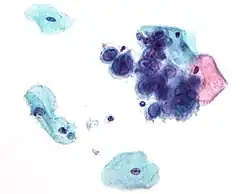

Размножение вирусов

Вирусы распространяются многими способами: вирусы растений часто передаются от растения к растению насекомыми, питающимися растительными соками, к примеру тлями; вирусы животных могут распространяться кровососущими насекомыми, такие организмы известны как переносчики. Вирус гриппа распространяется воздушно-капельным путём при кашле и чихании. Норовирус и ротавирус, обычно вызывающие вирусные гастроэнтериты, передаются фекально-оральным путём при контакте с заражённой пищей или водой. ВИЧ является одним из нескольких вирусов, передающихся половым путём и при переливании заражённой крови. Каждый вирус имеет определённую специфичность к хозяевам, определяющуюся типами клеток, которые он может инфицировать.